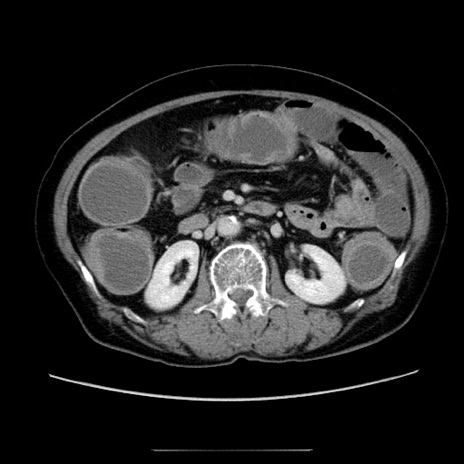

症例5(横断像)

【症例】70歳代女性

【主訴】お腹が張る

【現病歴】1週間くらい前から腹部膨満の自覚あり。昨日夜から増悪したため、本日救急外来受診。

【身体所見】意識清明、BT 36.5℃、BP 165/106mmHg、HR 80bpm、SpO2 98%、腹部:膨満、軟、自発痛・圧痛なし、触診にて不快感あり、腸蠕動音:減弱

【データ】WBC 12600、CRP 1.04